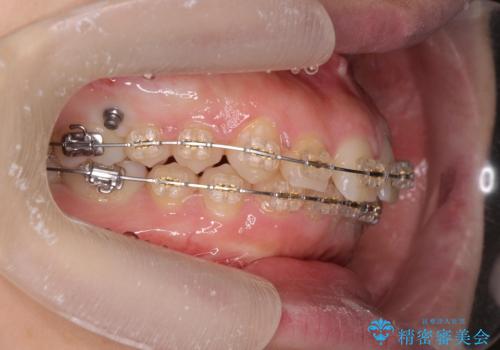

深い噛み合わせ、すきっ歯の改善 ワイヤーを用いたマルチブラケット矯正

- 矯正装置

- ワイヤー矯正

- 噛み合わせが深く、前歯が突き出て隙間が出てきたことの改善を希望され矯正治療の相談で当院に初診来院されました。

ワイヤーを用いたマルチブラケット矯正を行うことで深い噛み合わせを改善し、前歯の隙間もなくし審美的な歯列へと治療をおこなっていきます。